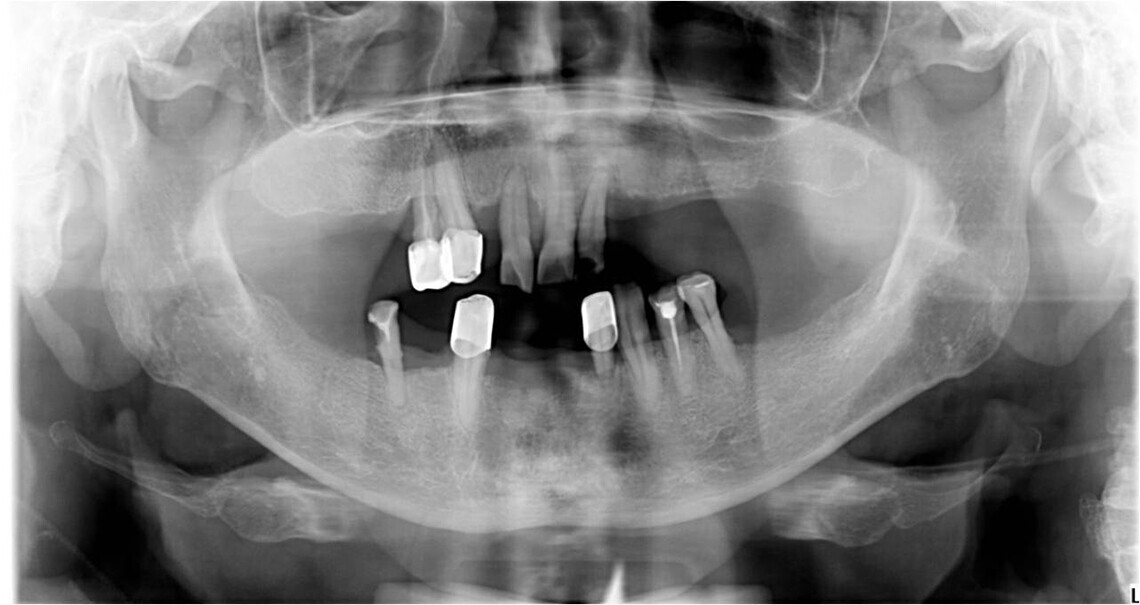

Съемная часть протеза надежно фиксируется на опорных зубах и имплантатах, покрытых первичными коронками. Опорные зубы или имплантаты при использовании бюгельного протеза на телескопических коронках не перегружаются.

Прочность фиксации конструкции зависит от количества опорных зубов или имплантатов. Для более надежной фиксации и продолжительного срока службы бюгельной конструкции требуется установка на челюсти не менее шести телескопов. Однако, чтобы зафиксировать телескопические протезы, достаточно двух опорных зубов или имплантатов.